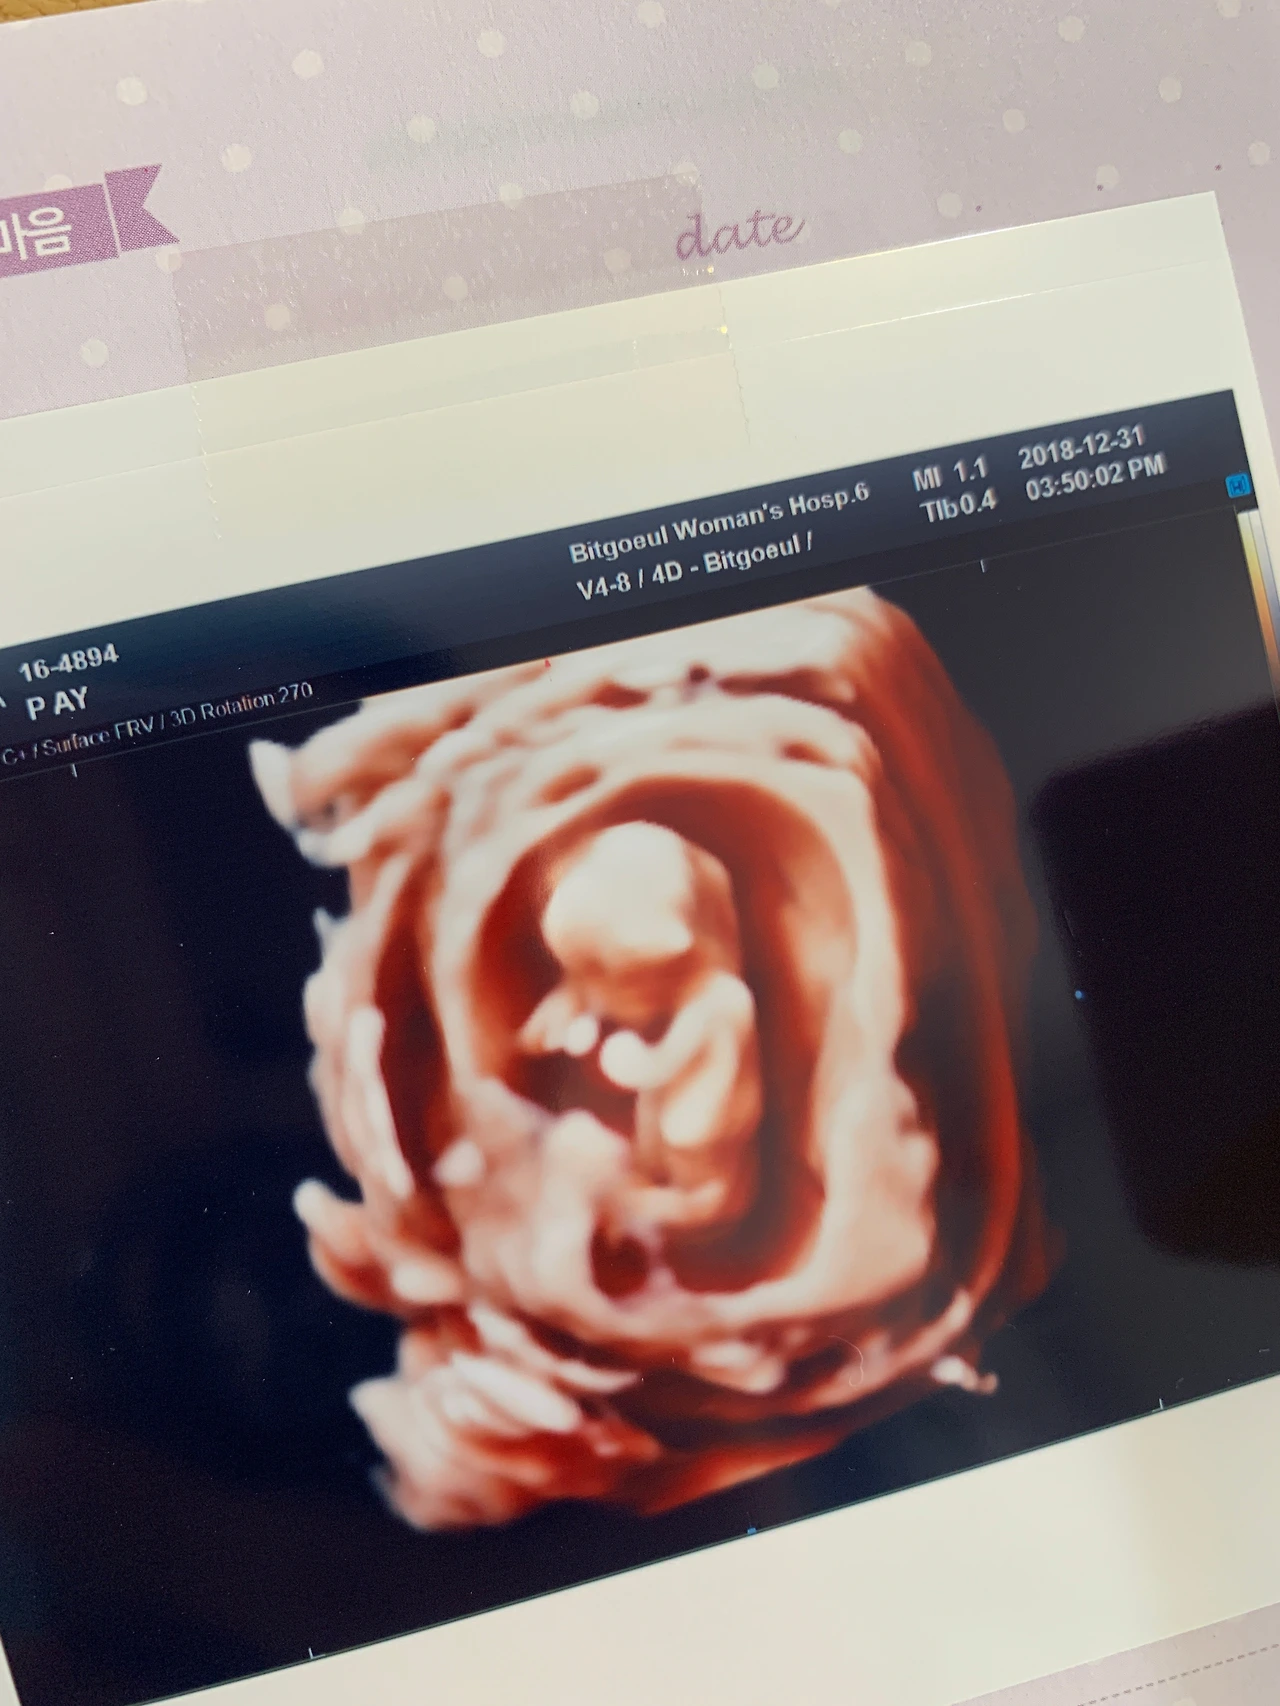

2차 기형아 검사도 받고, 기다리던 초음파를 보았다.

(꼬물꼬물 내 아가, 잘 크고 있으렴^^)